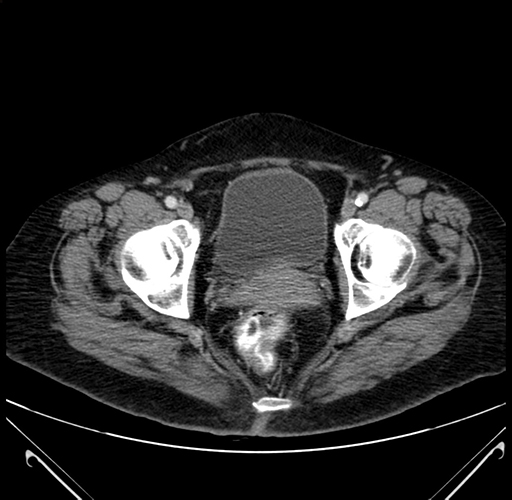

Axial Venous